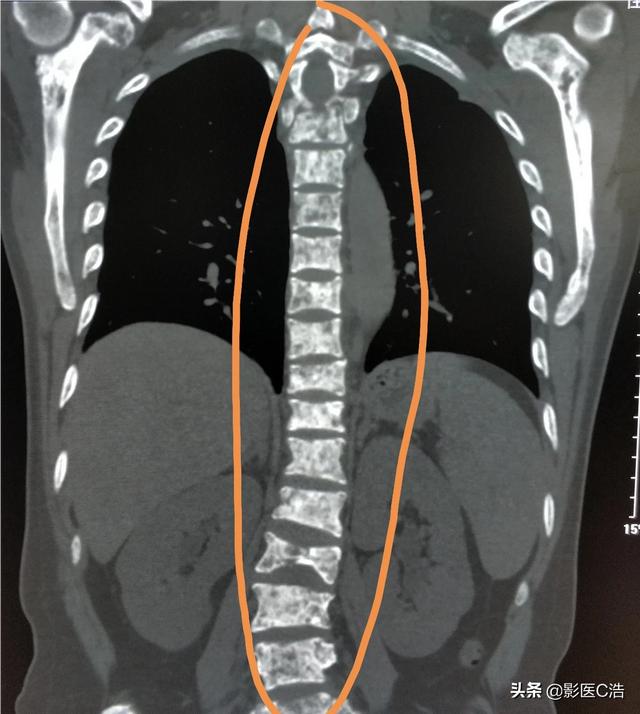

骨転移はどのような痛みに注意すべきですか?骨転移は悪性腫瘍の末期によく見られる症状で、体の他の部位にある原発腫瘍が血液やリンパ液の経路を通って骨に転移し、骨転移を形成することを指します。骨転移は、正常な骨組織が破壊され、腫瘍組織に置き換わっていることを示す。骨転移は病変の特異性により、溶骨型、造骨型、混合型の3つに分類される。骨転移の好発部位は中軸骨(脊椎、骨盤)、肋骨、下部骨幹部で、特に中軸骨が最も多く、これはこの部位の血液供給の特徴と関係しています。下の円のように骨転移が多発し、脊椎の状態が悪い。

骨転移で起こる症状にはどのようなものがありますか?最初の症状は痛みです。骨転移を起こした部位は骨が破壊されるために痛みを感じますが、最初ははっきりした症状がなかったり、断続的な痛みだったりしますが、腫瘍が正常な骨をどんどん破壊して徐々に悪くなっていくため、転移部位の痛みも徐々に悪くなっていきます。臨床的には、体のある部分の骨の痛みで、悪性腫瘍の骨転移という症例に出くわすことがあります。以前、ある症例に出会ったのですが、40歳で、肩が痛く、五十肩かと思い、薬用オイルを数日揉んでも改善が見られず、ますます痛みが強くなったので、病院で検査をしたところ、MRIを撮ったところ、肩甲骨が(腫瘍の)かけらに食べられており、骨転移を考え、胸部CTを撮ったところ、右肺に結節があり、生検をして病理検査をしたところ、肺がんの骨転移でした。その内容は以下の通りである。

胸椎に発生した骨転移性癌を示す。